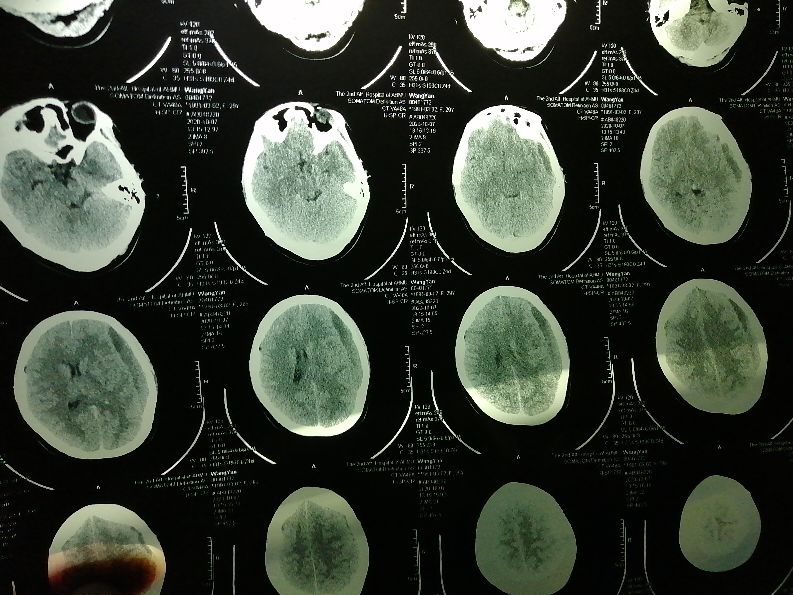

出院一个星期后头又开始疼了,期间对老婆好生照料,夜里根本不让她起来,因为医生说尽量平躺休息。可平躺也解决不了疼痛感,怎么也没也没想到后果这么严重,我也叫老婆去看看,可老婆坚持一个星期实在疼的不行才去的医院,谁又想去医院呢,月子都没出呢!去了医院先问的医生说挂神经内科,神经内科一下开了三个核共磁片子,结果是两天后才能做,因为门诊慢要预约,我问能不能提前做我老婆头疼的厉害,她说不行,得医生开单子才行。那时找医生也下班了,没办法只能等结果出来再来拿片子给医生看,医生直接领着我老婆去神经外科去看了,我那天出差没一起去看,老婆拿出打印出来的单子显示颅内硬膜下血肿,发给我看,我赶紧百度看了一下,好害怕,赶紧打电话就去问。医生看了片子也一顿吓唬我老婆,不能跌倒,不能碰,赶紧叫家人陪同住院啥的。听到这我急忙回去。我怎么也想不明白怎么会出现这样情况,心情很不好。一下是核磁结果图片。

住了院后又拍了一张脑部CT,说是观察,说等脑部血块变成血水才能开刀,我问医生怎么造成的,刚开始问就是说我老婆有没有外力造成的,我们实话实说在医院生产后就这样了,他之后就说什么原因都有可能,总结一句话不知道你是怎么造成的,但是能给你治好!我就笑了,省级最大最好的医院啊,不知道什么原因就去治病吗?!问了其他医生也是三缄其口。不能忍的我打了医患办的电话那时候9月28日,至今已经10天了,也没有给我回复半个电话!当时只是想着治好就行了,只要你们医生用点心就行了。不敢奢求什么。

9月30日CT结果